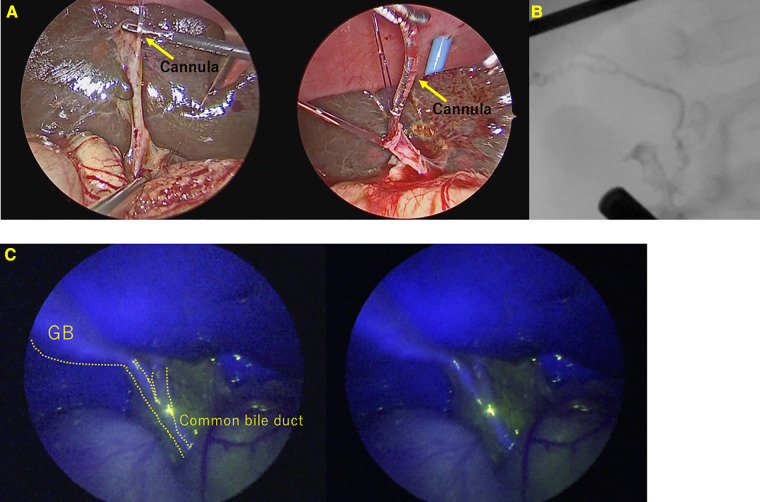

Conventional cholangiography was performed in all 23 cases that were not BA. Conventional cholangiography was extremely difficult in 2 of the 23 cases(8.7%) in whom BA was ruled out. In one case, the common hepatic duct could not be visualized. In another case, cannulation from the gallbladder was difficult to perform, although we managed to obtain contrast, ultimately requiring cholecystectomy. (Figure 3) In both cases where conventional cholangiography was difficult, both CBD and GB fluoresced clearly on ICG fluorescence cholangiography.

The prognosis of BA is known to be worse if definitive surgery is performed too late (ref. 1, ref. 2). However, a definitive diagnosis is difficult and often established based on intraoperative cholangiography and liver biopsy (ref. 3). Furthermore, conventional cholangiography requiring contrast injection through the gallbladder also presents technical challenges and imaging uncertainties (ref. 11, ref. 19). Therefore, it is anticipated that intraoperative cholangiography cannot be easily undertaken, even if BA is suspected. ICG fluorescence cholangiography can be easily performed with transvenous ICG injection and does not require cannulation through the atrophic gallbladder or retrograde cholangiography. Intravenous ICG fluorescent cholangiography is a minimally invasive and useful diagnostic method to exclude BA in infants with cholestasis, and we believe that conventional cholangiography should be performed only when this diagnostic method fails to make a diagnosis. If the GB is fluorescent, upstream contrast is not mandatory, even for conventional cholangiography (Figure 4). ICG fluorescence cholangiography makes performing intraoperative cholangiography easier than when conventional cholangiography was the only option, and it is expected to lead to earlier intraoperative cholangiography and curative surgery.